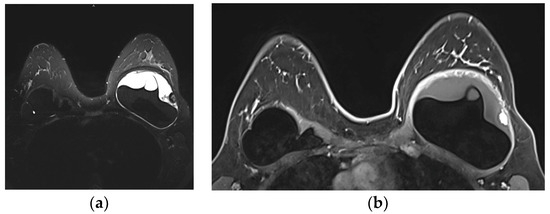

- Venkataraman, S.; Hines, N.; Slanetz, P.J. Challenges in mammography: Part 2, multimodality review of breast augmentation—Imaging findings and complications. Am. J. Roentgenol. 2011, 197, W1031–W1045. [Google Scholar] [CrossRef] [PubMed]

- Wong, T.; Lo, L.W.; Fung, P.Y.; Lai, H.Y.; She, H.L.; Ng, W.K.; Kwok, K.M.; Lee, C.M. Magnetic resonance imaging of breast augmentation: A pictorial review. Insights Imaging 2016, 7, 399–410. [Google Scholar] [CrossRef] [PubMed]

- Norena-Rengifo, B.D.; Sanin-Ramirez, M.P.; Adrada, B.E.; Luengas, A.B.; Martinez de Vega, V.; Guirguis, M.S.; Saldarriaga-Uribe, C. MRI for Evaluation of Complications of Breast Augmentation. Radiographics 2022, 42, 929–946. [Google Scholar] [CrossRef]

- Green, L.A.; Karow, J.A.; Toman, J.E.; Lostumbo, A.; Xie, K. Review of breast augmentation and reconstruction for the radiologist with emphasis on MRI. Clin. Imaging 2018, 47, 101–117. [Google Scholar] [CrossRef]